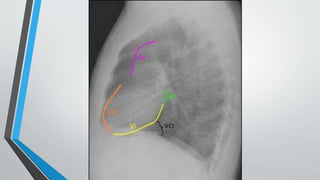

La insuficiencia cardiaca se define como la incapacidad del corazón para bombear sangre a una velocidad y cantidad adecuadas. Las causas afectan primero al ventrículo izquierdo y luego al derecho, resultando en insuficiencia ventricular. La radiología puede detectar signos de cardiomegalia, edema pulmonar, derrame pleural y patrón de "alas de mariposa". El índice cardiotorácico mide el grado de cardiomegalia y es útil para el diagnóstico de insuficiencia cardiaca.